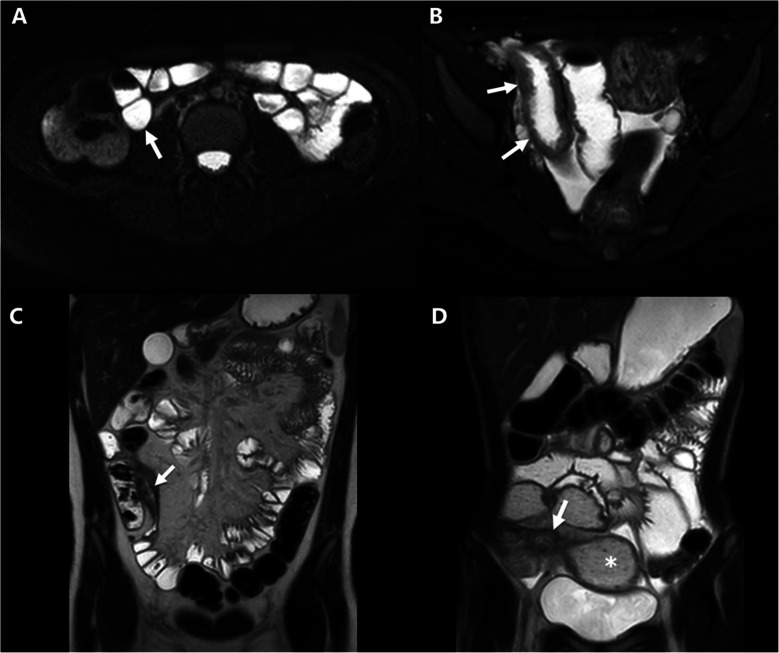

背景:横断面成像越来越多地用于克罗恩病的初始诊断和长期监测。回肠末端的定量形态学可以预测治疗效果。目的:我们旨在确定与克罗恩病儿童大队列临床和放射学治疗反应相关的基线定性和定量影像学特征。材料和方法:这是一项针对儿童克罗恩病的风险队列研究的回顾性研究。本多中心研究纳入1136名儿童。结果:纳入96名受试者。38% (n=36)的参与者达到了临床缓解终点,只有20% (n=19)的参与者达到了影像学正常化。随访影像显示24例(25%)患者疾病进展,其中7例(7%)在基线时放射学正常(7%)。较高的基线TI分类评分与随访期间影像正常化的几率较低相关(OR 0.4 [0.2, 0.8], P=0.009)。较大的TI最小管腔直径(OR 1.1 [1.01, 1.3], P=0.04)和较小的基线肠壁最大厚度(OR 0.8 [0.6, 0.97], P=0.03)与影像学正常化相关。没有与临床反应相关的基线影像学测量。结论:基线回肠末端最小管腔直径增加和壁厚减少与随访时的影像学正常化有关,但与临床反应无关。

Materials and methods: This was a retrospective study of the RISK cohort study in pediatric Crohn's disease. This multicenter study included 1,136 children <18 years from 28 sites in North America. Subjects enrolled with newly diagnosed Crohn's disease who underwent endoscopy with baseline and follow-up CT or MRI were considered for this study. Exclusion criteria were incomplete data or surgical resection prior to follow-up imaging. Imaging analysis included assessing a qualitative terminal ileum (TI) categorical score based on SAR-AGA consensus definitions ((1) normal, (2) inflammation only without luminal narrowing, (3) inflammation with luminal narrowing, or (4) stricture with pre-stenotic dilation ≥3 cm) and quantitative measurements (maximum bowel wall thickness and maximum/minimum lumen diameter). Two endpoints were considered: (1) clinical response (off corticosteroids and quiescent Physician Global Assessment at follow-up imaging) and (2) CT and MRI response (follow-up imaging normalization). Multivariable logistic regression analyses were developed for each endpoint.

Results: Ninety-six subjects were included. Clinical response endpoint was achieved in 38% (n=36) of participants, and imaging normalization was achieved in only 20% (n=19) of participants. Follow-up imaging showed disease progression in 24 (25%) patients, 7 (7%) of whom were radiologically normal at baseline (7%). A higher baseline TI categorical score was associated with lower odds of imaging normalization during follow-up (OR 0.4 [0.2, 0.8], P=0.009). Larger TI minimum lumen diameter (OR 1.1 [1.01, 1.3], P=0.04) and smaller maximum bowel wall thickness at baseline (OR 0.8 [0.6, 0.97], P=0.03) were associated with imaging normalization. There were no baseline imaging measurements associated with clinical response.